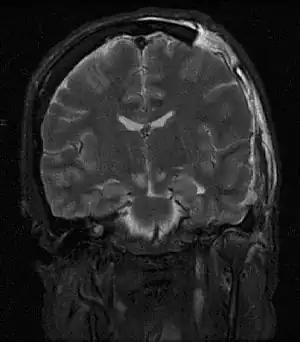

Brain herniation is a potentially deadly side effect of very high pressure within the skull that occurs when a part of the brain is squeezed across structures within the skull. The brain can shift across such structures as the falx cerebri, the tentorium cerebelli, and even through the foramen magnum (the hole in the base of the skull through which the spinal cord connects with the brain). Herniation can be caused by a number of factors that cause a mass effect and increase intracranial pressure (ICP): these include traumatic brain injury, intracranial hemorrhage, or brain tumor.[1]

Herniation can also occur in the absence of high ICP when mass lesions such as hematomas occur at the borders of brain compartments. In such cases local pressure is increased at the place where the herniation occurs, but this pressure is not transmitted to the rest of the brain, and therefore does not register as an increase in ICP.[2]

Because herniation puts extreme pressure on parts of the brain and thereby cuts off the blood supply to various parts of the brain, it is often fatal. Therefore, extreme measures are taken in hospital settings to prevent the condition by reducing intracranial pressure, or decompressing (draining) a hematoma which is putting local pressure on a part of the brain.

Treatment involves removal of the etiologic mass and decompressive craniectomy. Brain herniation can cause severe disability or death. In fact, when herniation is visible on a CT scan, the prognosis for a meaningful recovery of neurological function is poor.[2] The patient may become paralyzed on the same side as the lesion causing the pressure, or damage to parts of the brain caused by herniation may cause paralysis on the side opposite the lesion.[11] Damage to the midbrain, which contains the reticular activating network which regulates consciousness, will result in coma.[11] Damage to the cardio-respiratory centers in the medulla oblongata will cause respiratory arrest and (secondarily) cardiac arrest.[11] Investigation is underway regarding the use of neuroprotective agents during the prolonged post-traumatic period of brain hypersensitivity associated with the syndrome.[17]